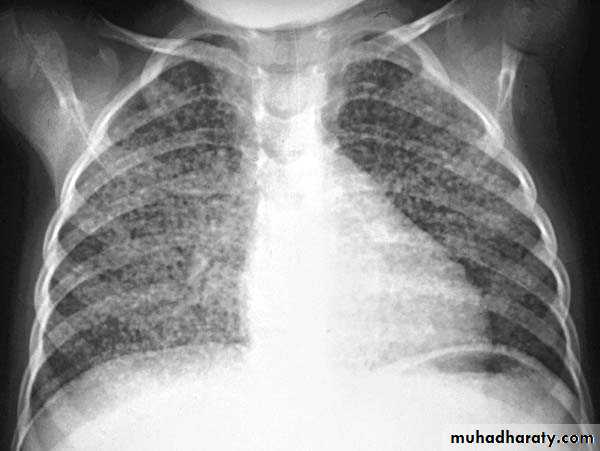

Miliary TB

65.Miliary TB

66.miliary TB